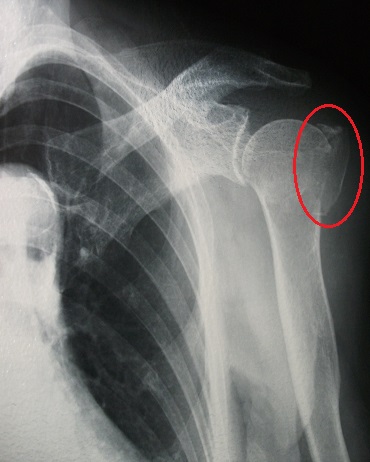

大結節骨折 画像診断key Book トレーニング 造影剤と画像診断情報サイト Bayer Radiology

大結節骨折 画像診断key Book トレーニング 造影剤と画像診断情報サイト Bayer Radiology